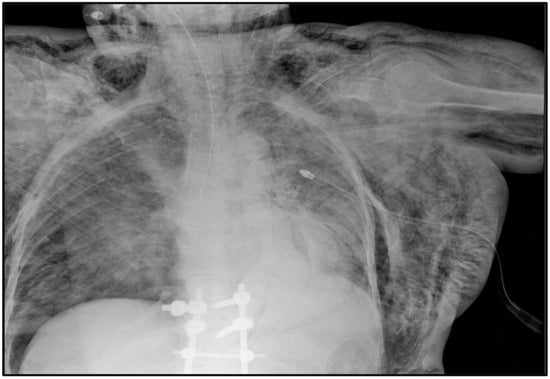

2.2. Case #2